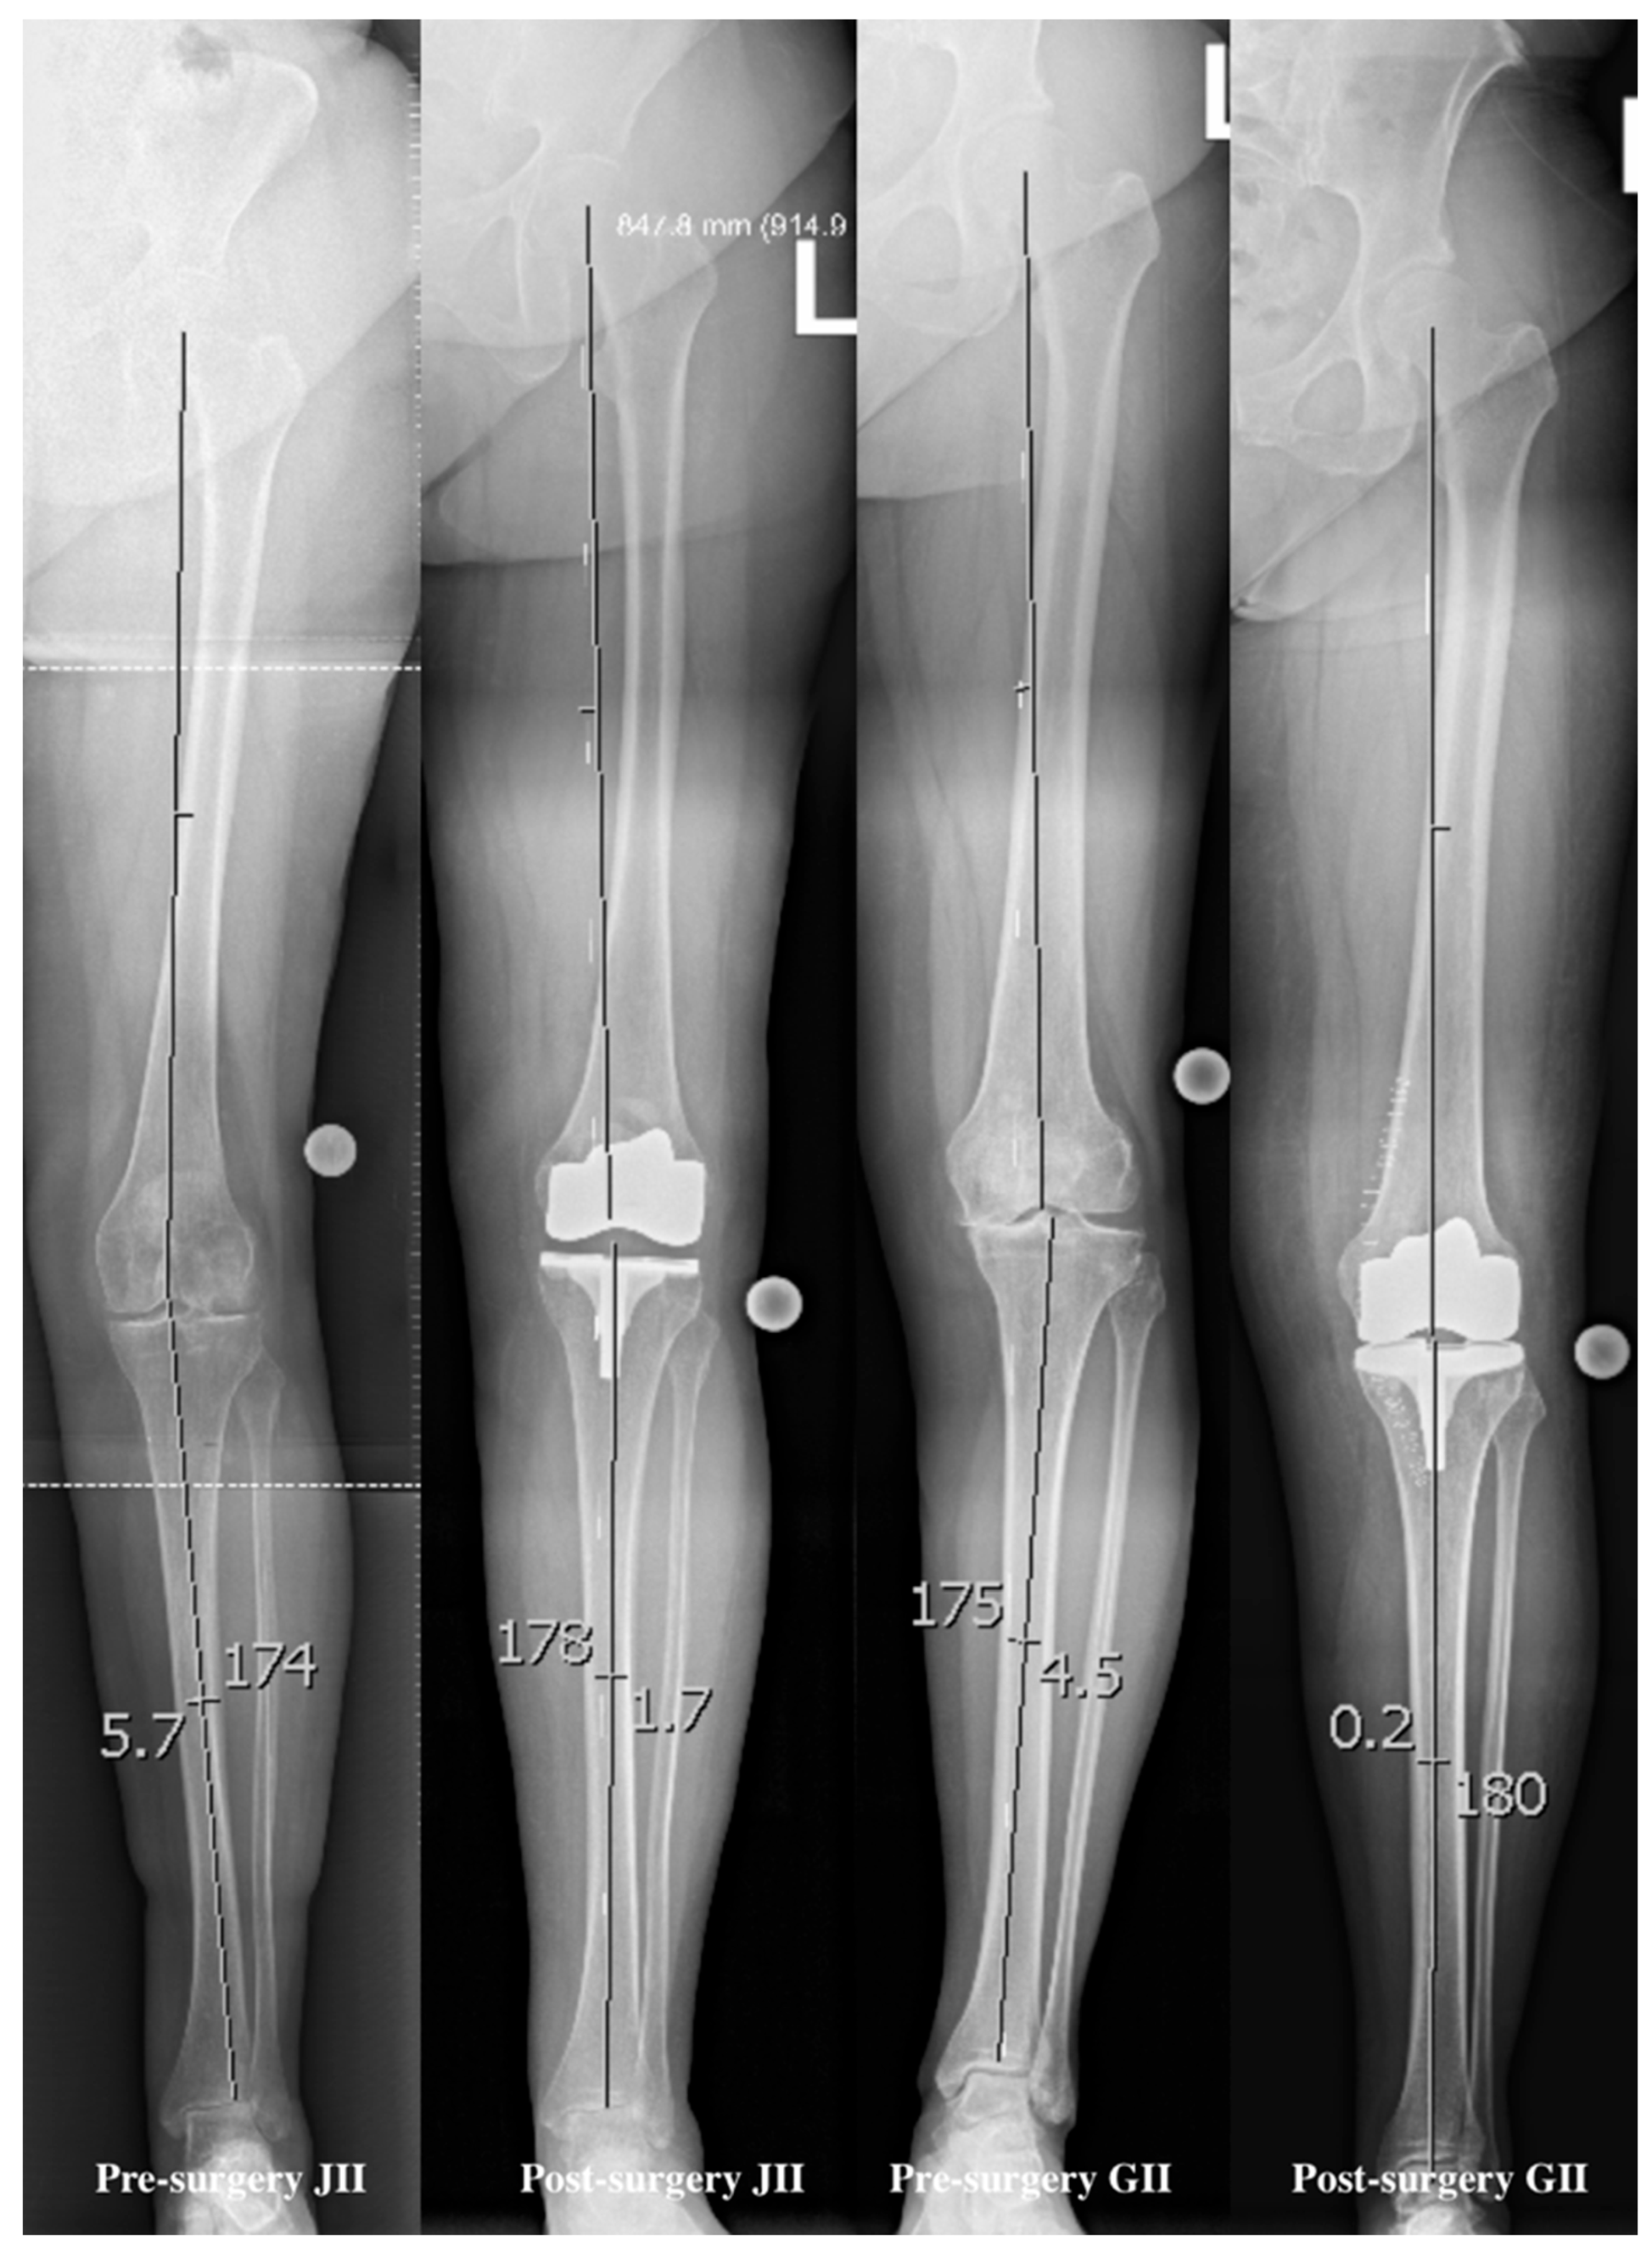

The degree correction of the axial misalignments (alpha-angle) was measured before and after, based on the work of Poilvache et al. (1996) [17]. Overall, the preoperative axis was significantly different to the postoperative axis and the axis after six months in the control (p = 0.001, 95%CI = 3.8021/6.0966; p = 0.001, 95%CI = 3.9005/6.2514), but no difference was found between the postoperative control and the six month control of the axis (p = 0.444, 95%CI = −0.6389/0.2831) (see Figure 2 for details). In general, patients with a higher postoperative axis were more satisfied with the arthroplasty after 6 months (p = 0.039, 95%CI = 0.006/0.435).

Figure 2. Examples of angle measuring, pre- and postoperatively, with the JII and GII arthroplasty. The fixed points were the hip joint center of rotation, the distal femoral center, the proximal tibial center, and the distal tibial center.